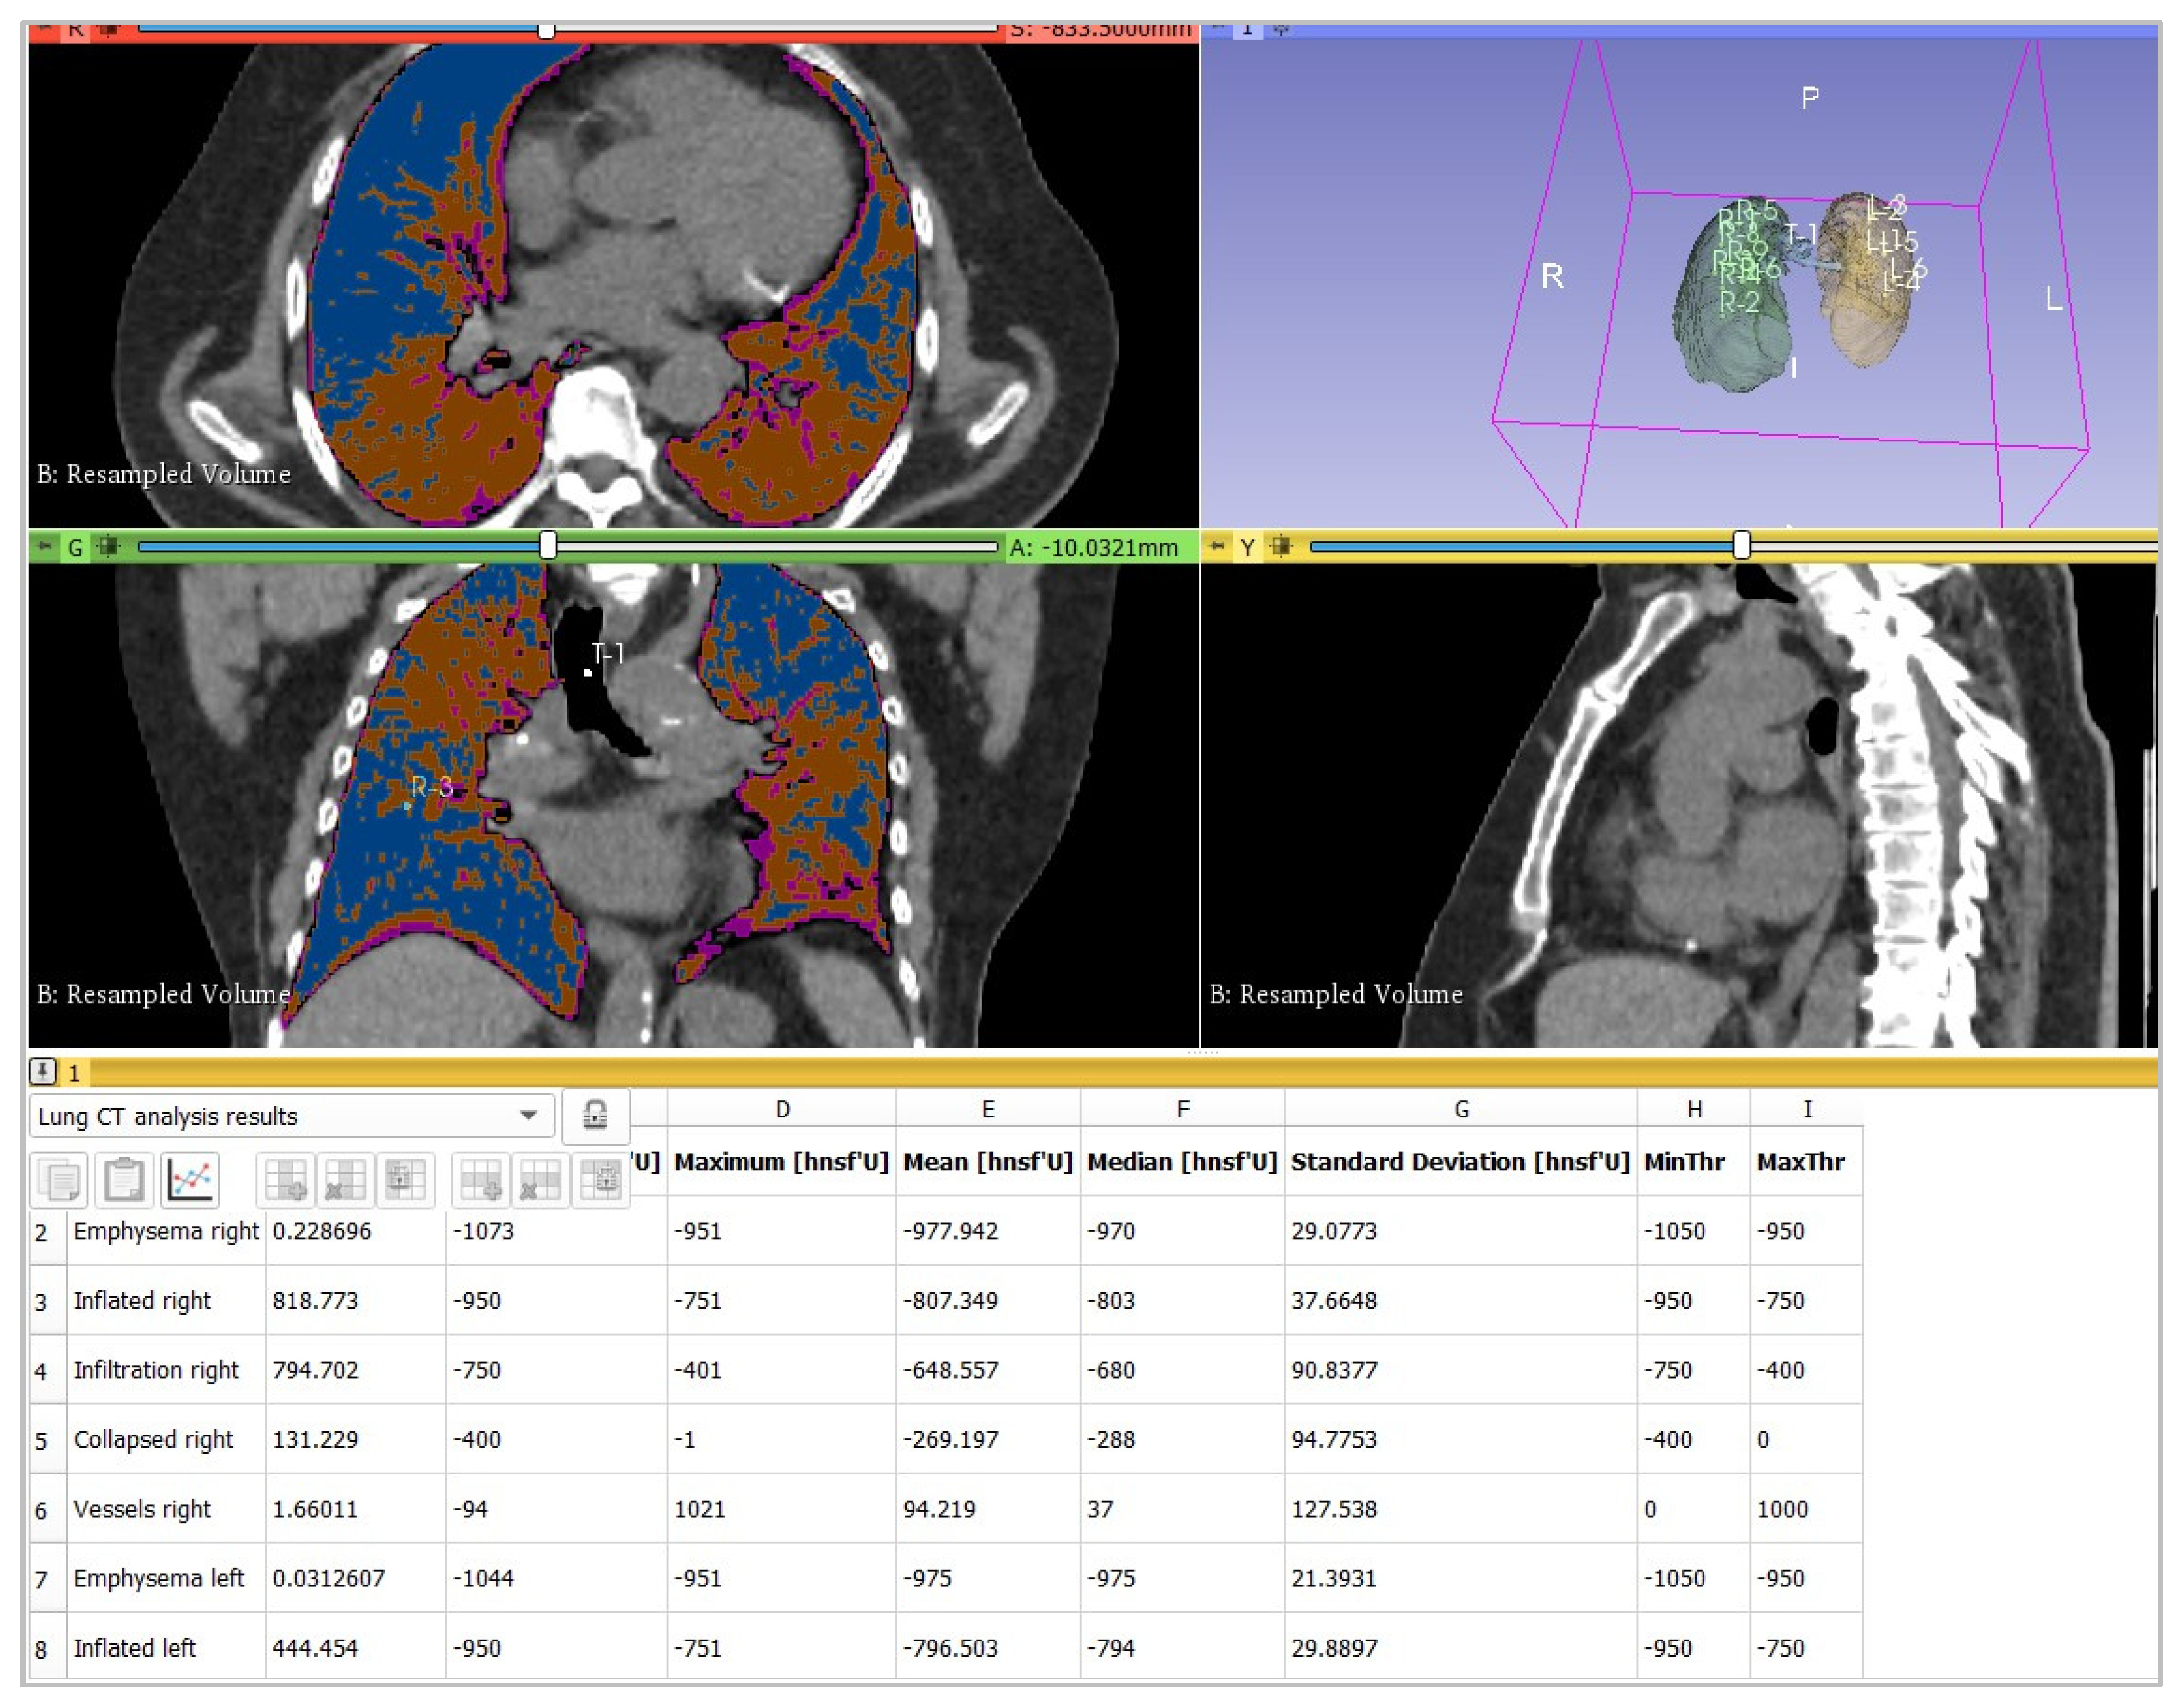

2.3. Image Analysis

- -

| 3DSlicer | 27 | 35 | 46 |

| Canon | 22 | 32 | 43 |

| Siemens | 24 | 32 | 42 |

| ICC = 0.92 | |||

| LungCTAnalyzer | 3DSlicer | 35 | 23 | 0.75 |

| CT Lung Density Analysis | Canon | 32 | 23 | 0.74 |

| CT Pulmo 3D | Siemens | 32 | 23 | 0.70 |

| Parenchyma Analysis | 3DSlicer | 25 | 23 | 0.69 |